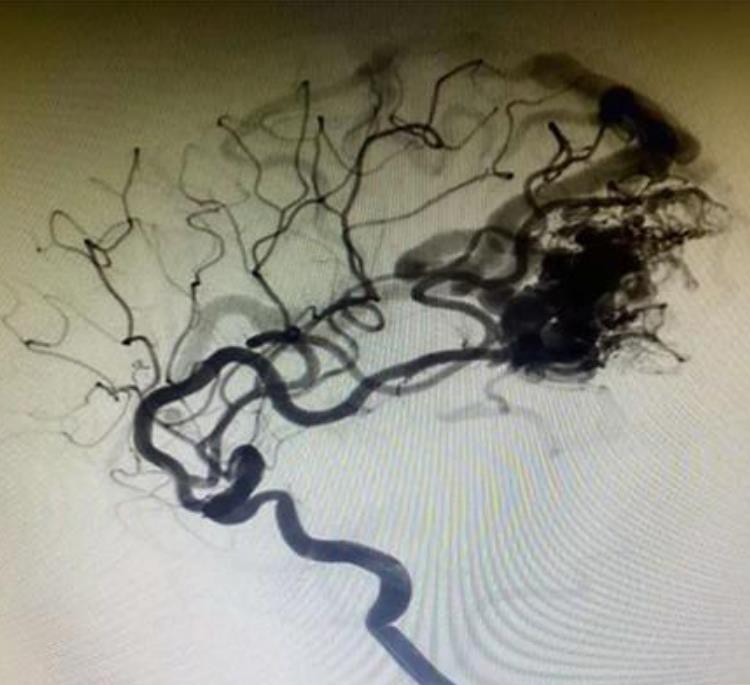

লাভা -12 ইন্ট্রাক্রানিয়াল অ্যানিউরিজমস তরল এম্বোলিক সিস্টেম

ট্যানটালাম পাউডারটি আরও সূক্ষ্ম, আরও ধীরে ধীরে বৃষ্টিপাত এবং আরও স্পষ্টভাবে রেডিওগ্রাফি প্রতিযোগীদের সাথে তুলনা করে।